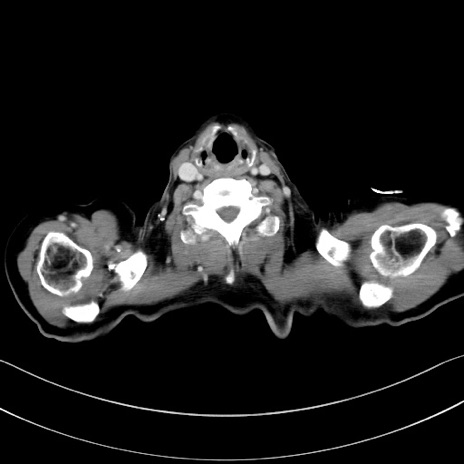

症例28(横断像)

【症例】60歳代男性

【主訴】嘔吐

【現病歴】胃癌にて胃全摘後。食思不振が悪化し、夜中に嘔吐することがある。

【既往歴】胃癌、胃全摘、脾摘、胆摘後

【データ】WBC 5900、CRP 10.56